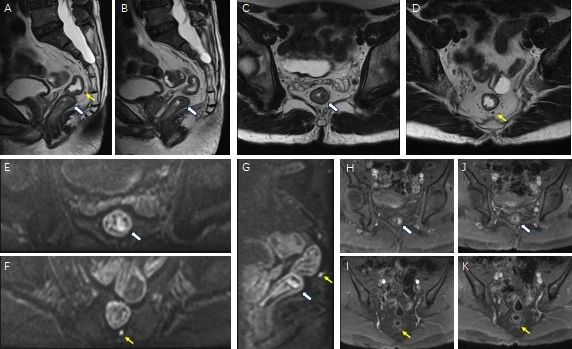

随后,刘先生来到瑞金医院放射科,张欢医生对刘先生使用了“神器”——直肠MR进行探查,结果显示他的直肠中段粘膜下有病变,直肠系膜内有一枚小淋巴结,转移性可能大。

(T2加权成像示稍低信号的病灶位于中段直肠粘膜下10*6mm(白色箭头),直肠系膜内一枚小淋巴结显示,截面大小约3.3*2.6mm(黄色箭头)边界略欠清。增强早期病灶及小淋巴结明显强化,而后强化程度有所减低。故MR诊断为直肠中段粘膜下病变,直肠系膜内一枚小淋巴结显示,转移性可能大。)